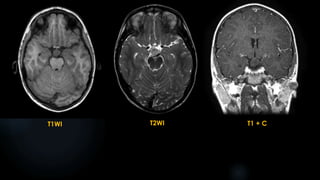

Atypical Teratoid Rhabdoid Tumor

 uncommon malignant intracranial tumors, representing only 1.3% of primary CNS tumors in the

pediatric population (WHO Grade IV tumour)

 vast majority of cases occurs in young children less than two years of age

 can occur anywhere in the central nervous system (CNS) including the spinal cord.

 infratentorial: ~50%

 - cerebellum (most common), brainstem

 supratentorial

 - cerebral hemispheres, pineal gland region, septum pellucidum and hypothalamus

ATRT (contd.)

 CT :

 often isodense to gray matter

 may demonstrate heterogeneous enhancement

 calcification is common

 may show associated obstructive hydrocephalus

 MRI:

 Can show necrosis, multiple foci of cyst formation and sometimes haemorrhage:

 T1: iso- to slightly hyperintense to grey matter (haemorrhagic areas can be more hyperintense)

 T2: generally hyperintense (haemorrhagic areas can be hypointense)

 T1 C+ (Gd): heterogeneous enhancement

 MRS

- Cho: elevated

- NAA: decreased

Differential diagnosis for ATRT:

 Supratentorial PNET

 Intracranial teratoma

 Medulloblastoma

 Choroid plexus carcinoma

 Malignant glioma